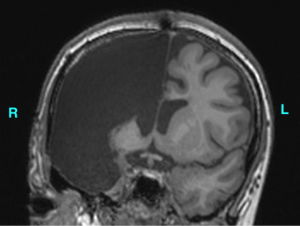

Perhaps there is no more remarkable example of brain plasticity and human adaptation than hemispherectomy. Hemispherectomy, surgical removal (or disconnection) of an entire cortical hemisphere, is conducted to treat severe epilepsy. It is a radical procedure, that is typically deemed ‘successful' if seizures cease. However, very little is known about how the neural system adapts to this change, nor about the long-term impact of this procedure on cognitive and social functioning.